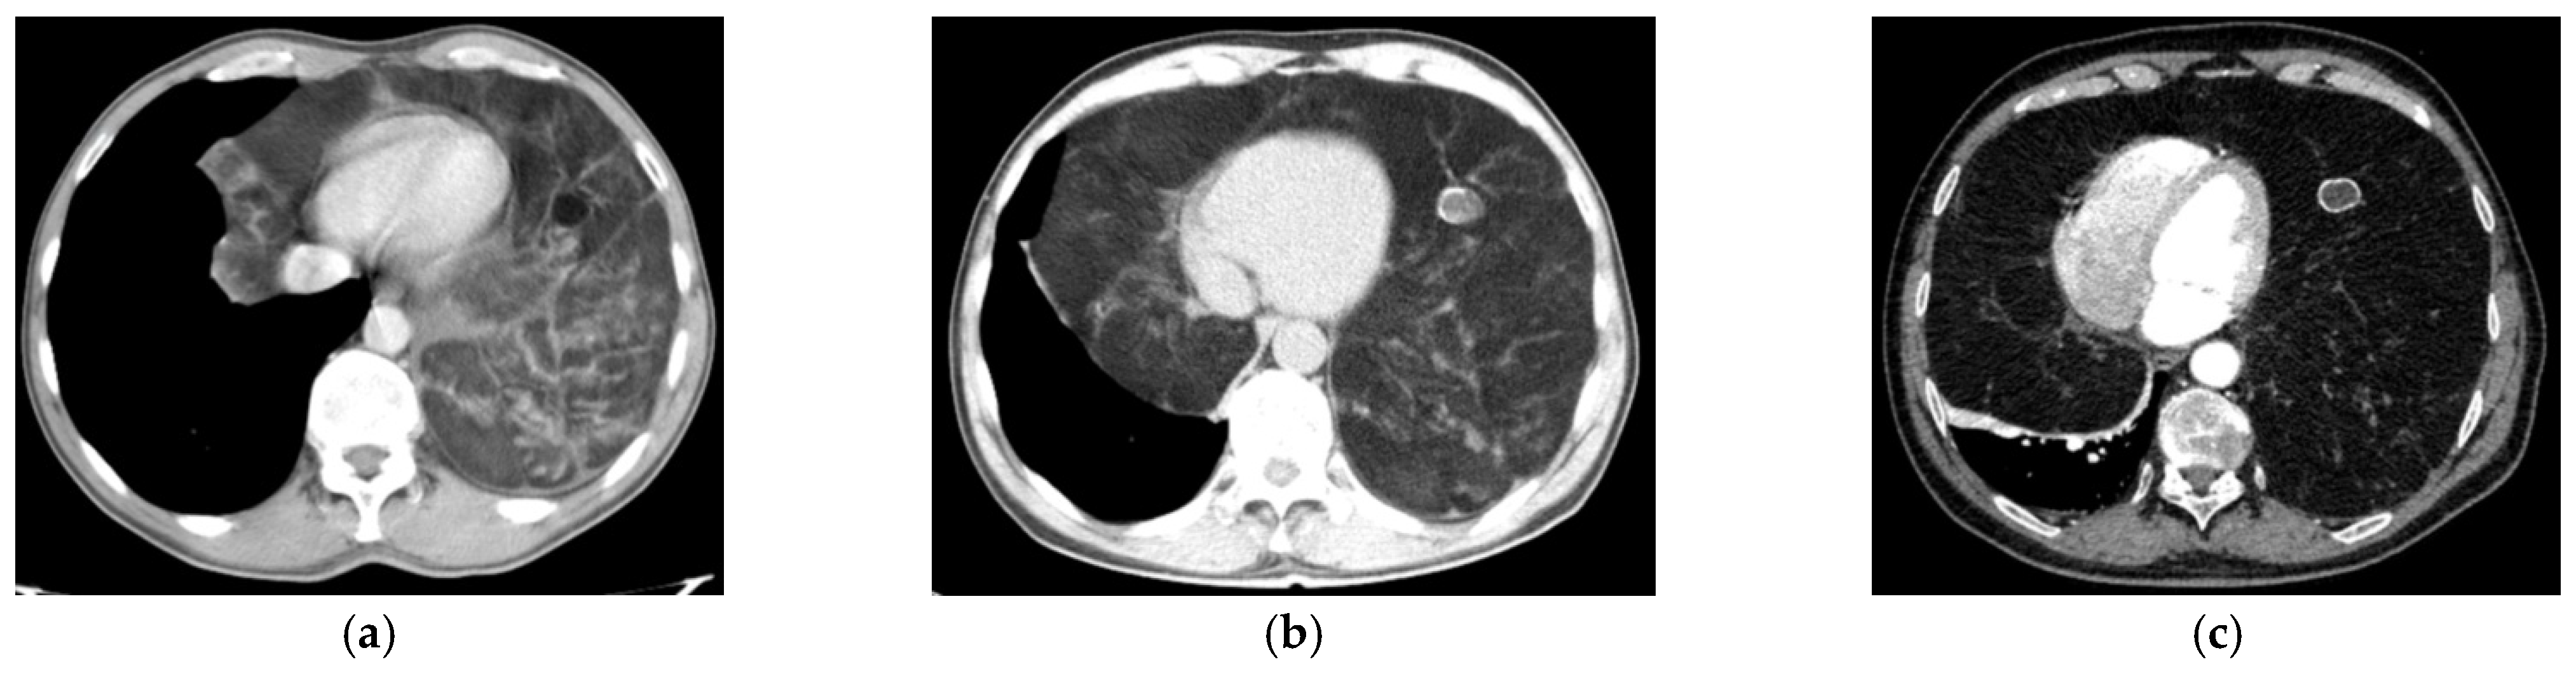

| CRC 1 (minimal compression) |

|

| CRC 2 (moderate compression) |

| CRC 3 (“giant mediastinal tumor”) | |

| CRC 3A |

| CRC 3B |